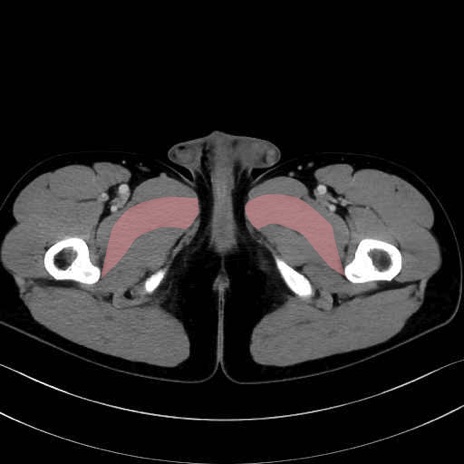

短内転筋(Adductor brevis) のCT画像の解剖

短内転筋 (Adductor brevis)